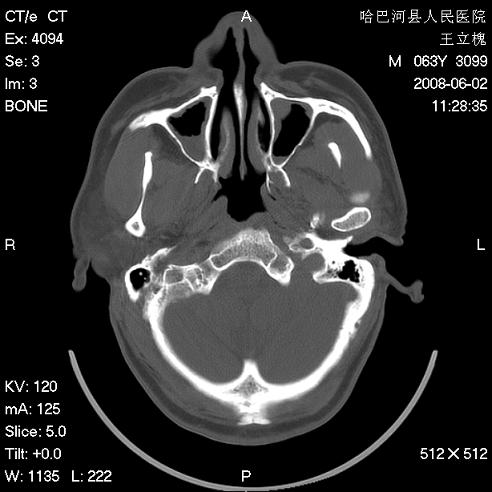

标题: CT13803:反复性鼻塞、流涕一年余 [打印本页]

标题: CT13803:反复性鼻塞、流涕一年余

副鼻窦炎,右上额窦积脓。左眼肌锥内见致密影,视神經受压

全组副鼻窦炎 肌锥内高密度灶。建议进一步检察检查

2、左眼眶肌锥内病变,小血管瘤?建议增强。

2、左眼眶肌锥内病变,建议增强

1)全副鼻窦炎(左侧上颌窦黏膜下囊肿或息肉)。2)左眼眶肌锥内不规则小结节状软组织密度影;考虑为小血管瘤可能。建议行ct增强扫描检查。

全组副鼻窦炎,左侧肌锥内不规则形软组织肿块影,与眼外肌密度相当,左侧视神经受压,肿块与视神经及眼外肌分界清晰,眼外肌无增粗,眶壁无破坏,球后脂肪间隙不模糊,考虑良性改变,小血管瘤或神经源性肿瘤可能,建议增强扫描。

谢谢,增强扫描做了,眶内病灶与海绵窦同步明显强化,血管瘤